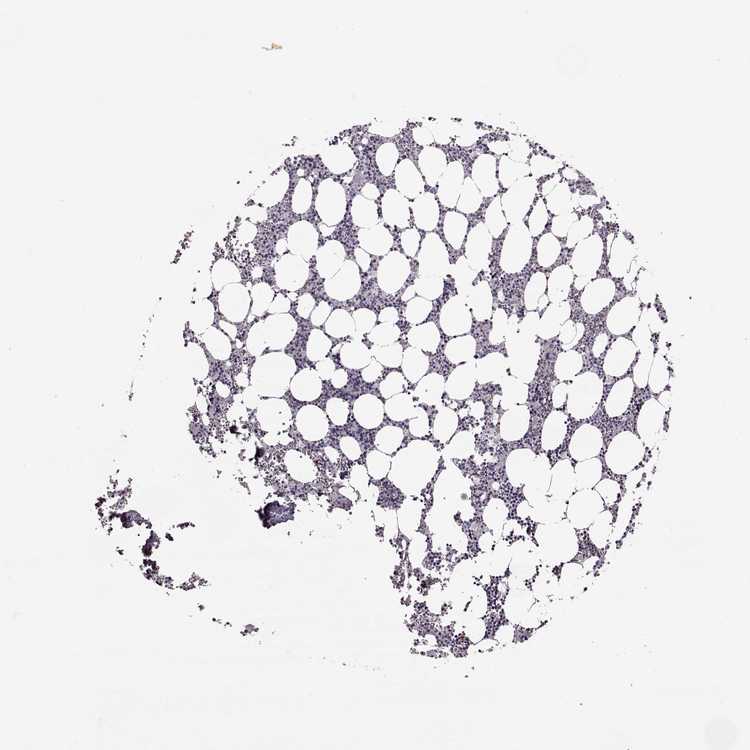

TISSUE PRIMARY DATA BONE MARROW Show tissue menu

BONE MARROW - Antibody stainingi

Antibody staining in the annotated cell types in the current human tissue is reported as not detected, low, medium, or high, based on conventional immunohistochemistry profiling in selected tissues. This score is based on the combination of the staining intensity and fraction of stained cells.

Each image is clickable and will lead to virtual microscopy that enables deeper exploration of all samples and also displays staining intensity scores, fraction scores and subcellular localization as well as patient and tissue information for each sample.

Antibody HPA023908

Hematopoietic cells Not detected